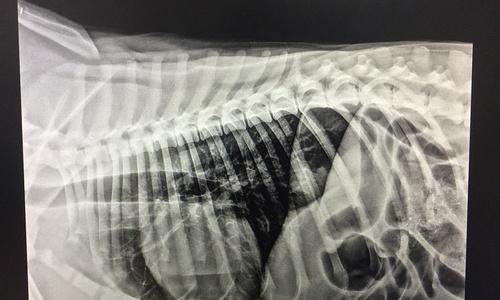

狗肠梗阻手术(了解狗肠梗阻手术后的恢复时间以及关键因素,让你的宠物更快康复)

狗肠梗阻是一种常见的狗病,如果不及时处理,可能会导致严重的并发症甚至危及生命。手术是治疗狗肠梗阻的一种有效方法,但手术后的恢复期和影响因素却鲜为人知。本文旨在介绍狗肠梗阻手术后的恢复情况,以及一些关键因素,帮助宠物主人更好地护理自己的宠物。